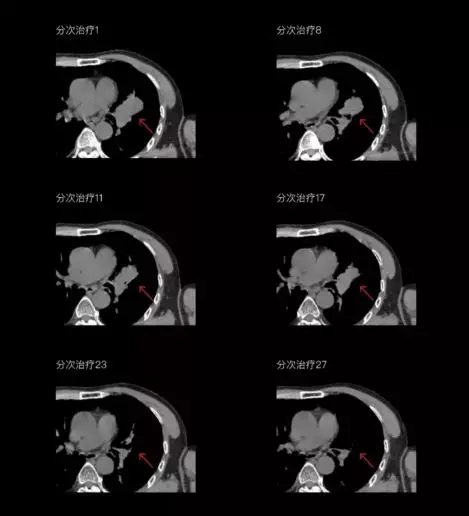

聯(lián)影CT-linac全程監(jiān)測(cè)治療過程病灶的變化,及時(shí)調(diào)整和優(yōu)化治療方案